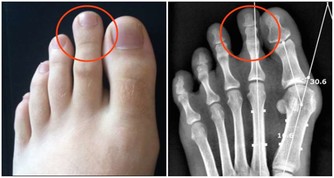

那麼哪些人患有二型糖尿病的機率更高呢?據統計,多數患者是在四十歲左右被確診;不過近些年來糖尿病的平均發病年齡越來越低,內分泌專家認為這與肥胖症的流行密不可分。過度肥胖的人對胰島素的敏感性會逐漸減弱,體內的胰島素受體數量也會減少,久而久之便會誘發二型糖尿病,所以肥胖這個誘因是不可忽視的。無論體重是否在正常範圍之內,都要注重膳食營養均衡,堅持鍛煉身體,保持健康的體型,遠離各類疾病的困擾。